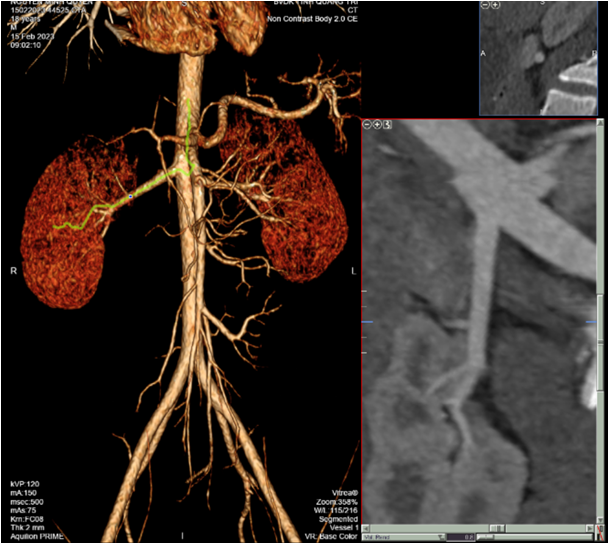

Trường hợp bệnh nhân N.M.Q, giới tính nam, 18 tuổi, vào viện với triệu chứng đái máu toàn bãi kéo dài khoảng một tuần kèm đau nhẹ từng cơn vùng hông trái. Khai thác tiền sử bệnh nhân có nhiều đợt đái máu tương tự, tự giới hạn trong khoảng hai đến ba ngày, không kèm theo các triệu chứng khác như sốt hay tiểu buốt, rát, gầy sụt cân…. Bệnh nhân được chỉ định làm các xét nghiệm máu, xét nghiệm nước tiểu, siêu âm bụng, Xquang bụng. Kết quả Xquang bụng không chuẩn bị không phát hiện thấy sỏi cản quang hệ tiết niệu. Kết quả siêu âm bụng cho thấy bệnh nhân có thận trái ứ nước độ I chưa rõ nguyên nhân. Nghi ngờ có bất thường mạch máu thận nên các bác sỹ đã cho chỉ định chụp cắt lớp vi tính hệ tiết niệu có dựng hình và khảo sát động mạch thận. Ghi nhận trên phim chụp CTscaner cho thấy: hình ảnh nhánh phụ động mạch thận trái xuất phát từ động mạch chủ bụng về phía đài dưới thận trái, giãn nhẹ bể thận trái do niệu quản xung đột với động mạch thận phụ, hai thận kích thước bình thường, không có sỏi. Từ kết quả chụp CTscaner các bác sĩ kết luận: bệnh nhân trên bị giãn bể thận trái do đoạn niệu quản xuất phát xung đột với động-tĩnh mạch thận phụ và tư vấn nên phẫu thuật ghép niệu quản để giải phóng tắc nghẽn.

Hình ảnh chụp CT dựng hình và khảo sát mạch thận.

Có thể thấy bệnh nhân trên xuất hiện thêm các nhánh động mạch thận phụ có xung đột với niệu quản gây ra tình trạng giãn đoạn bể thận phía trên kèm theo tình trạng đái máu tái phát.